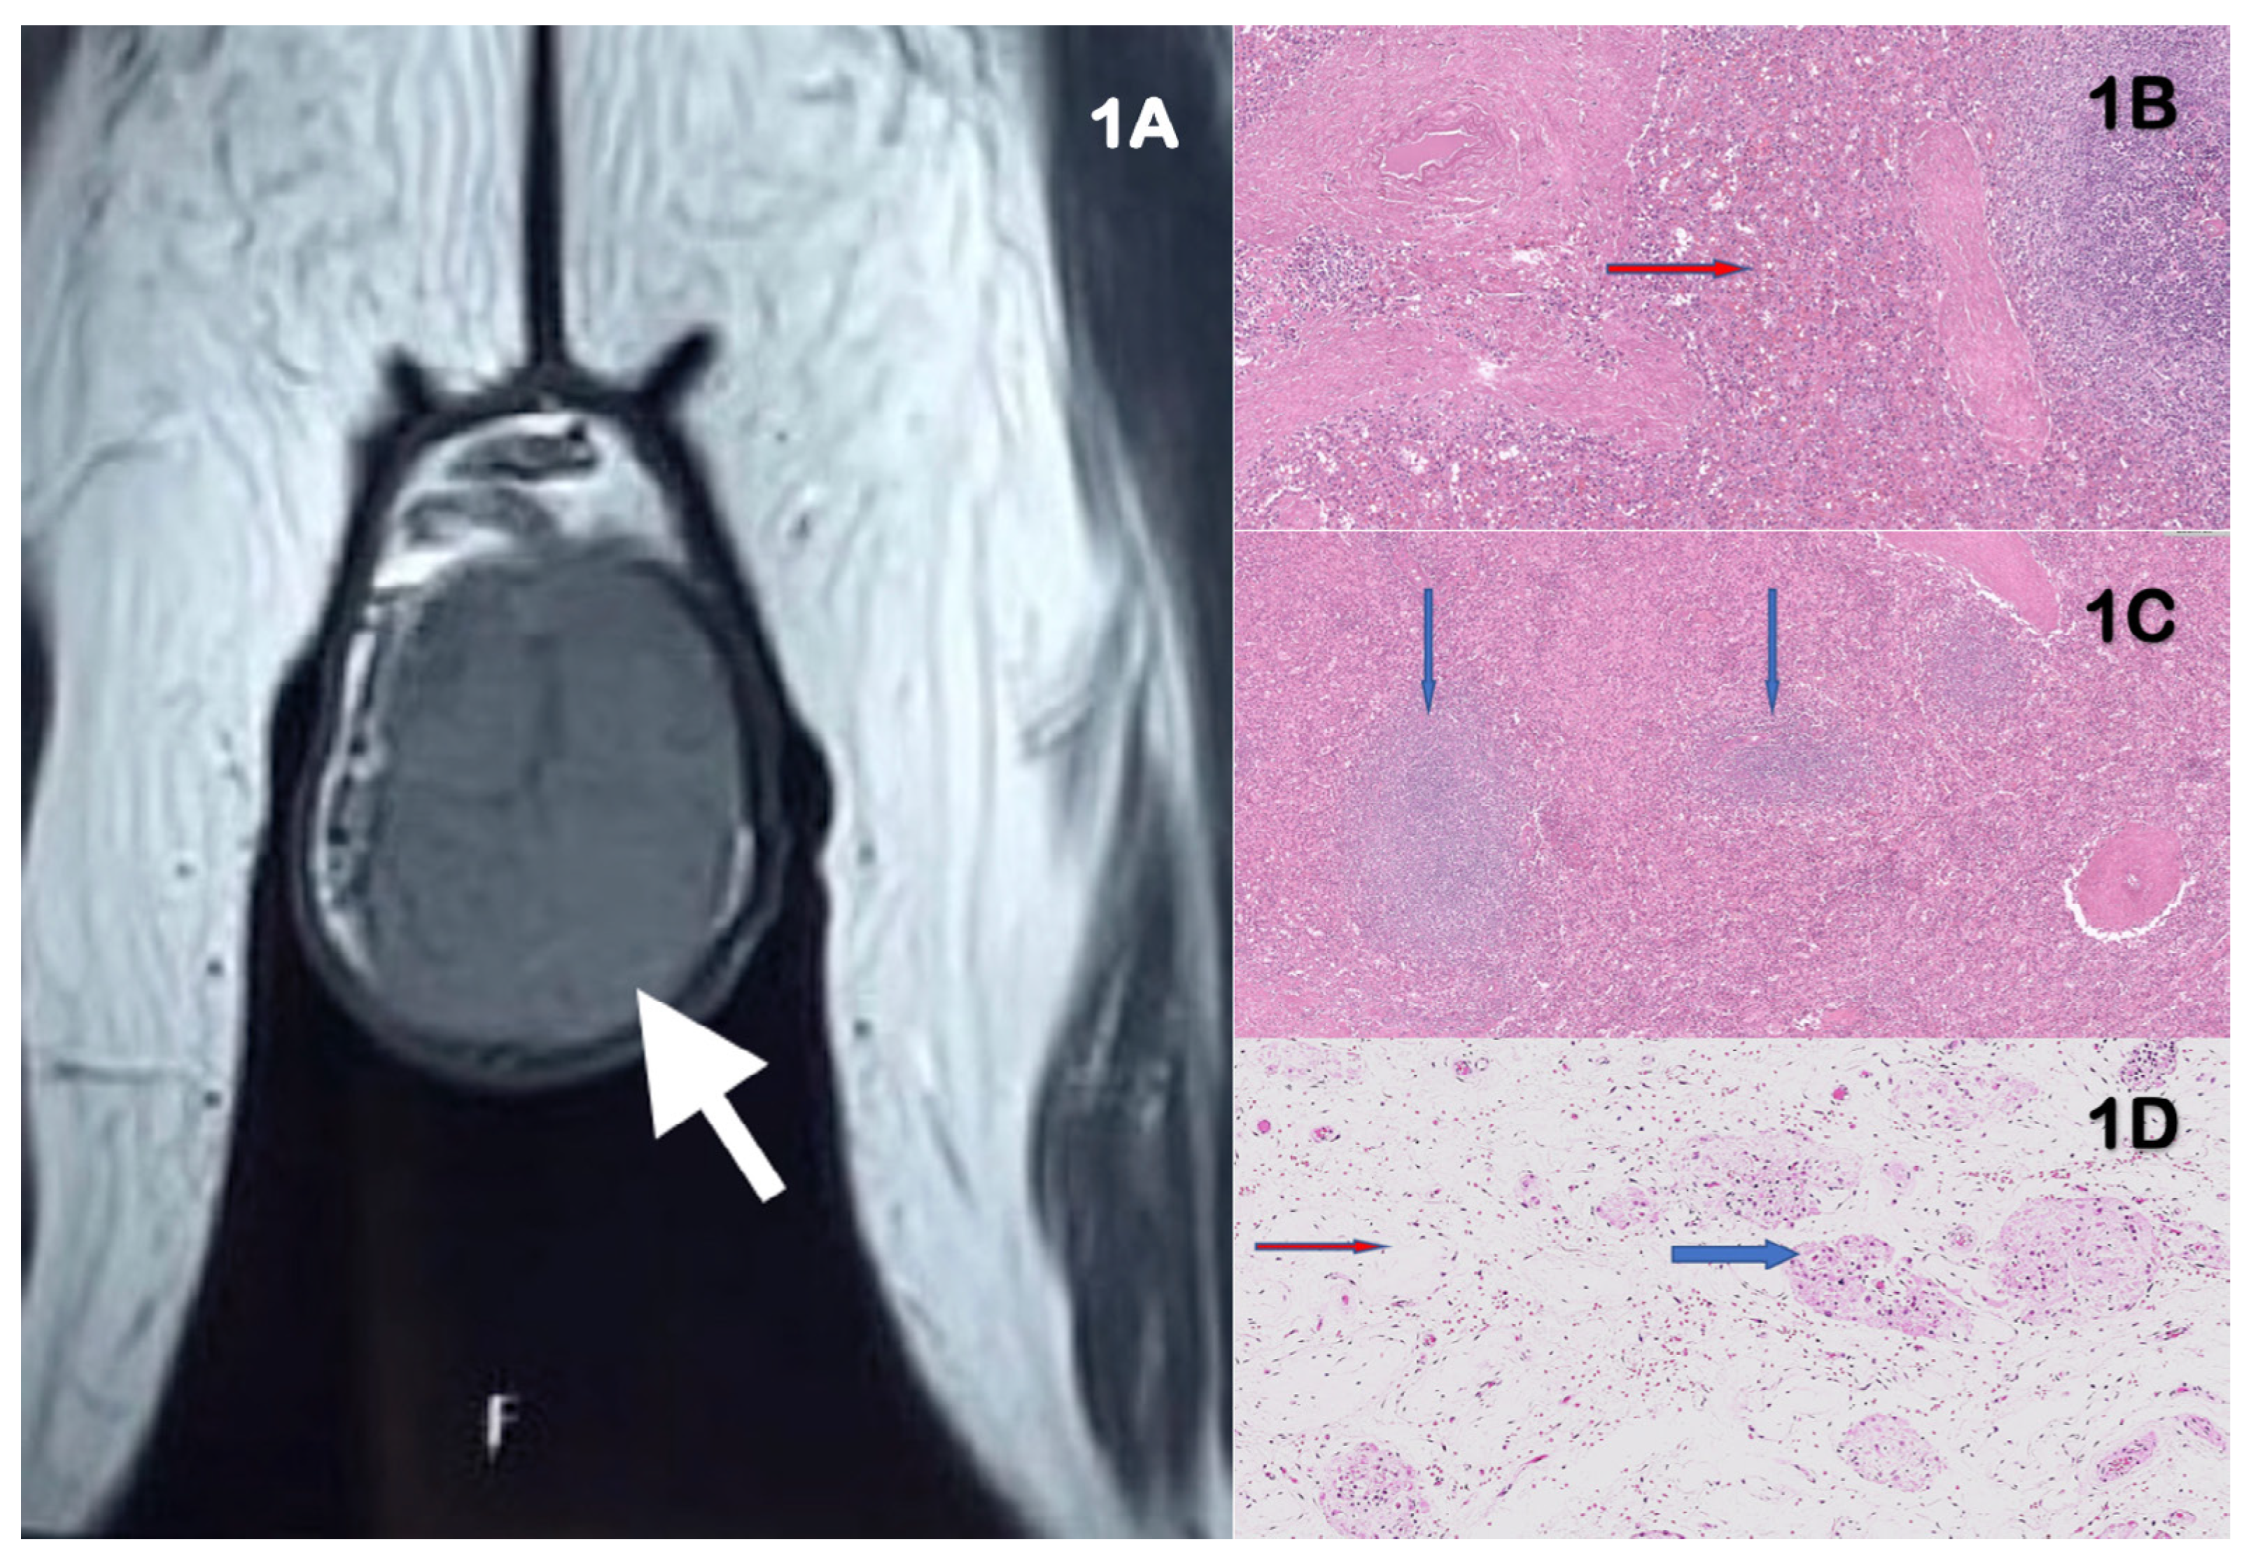

Large Accessory Scrotal Spleen Masquerading as Testicular Tumor